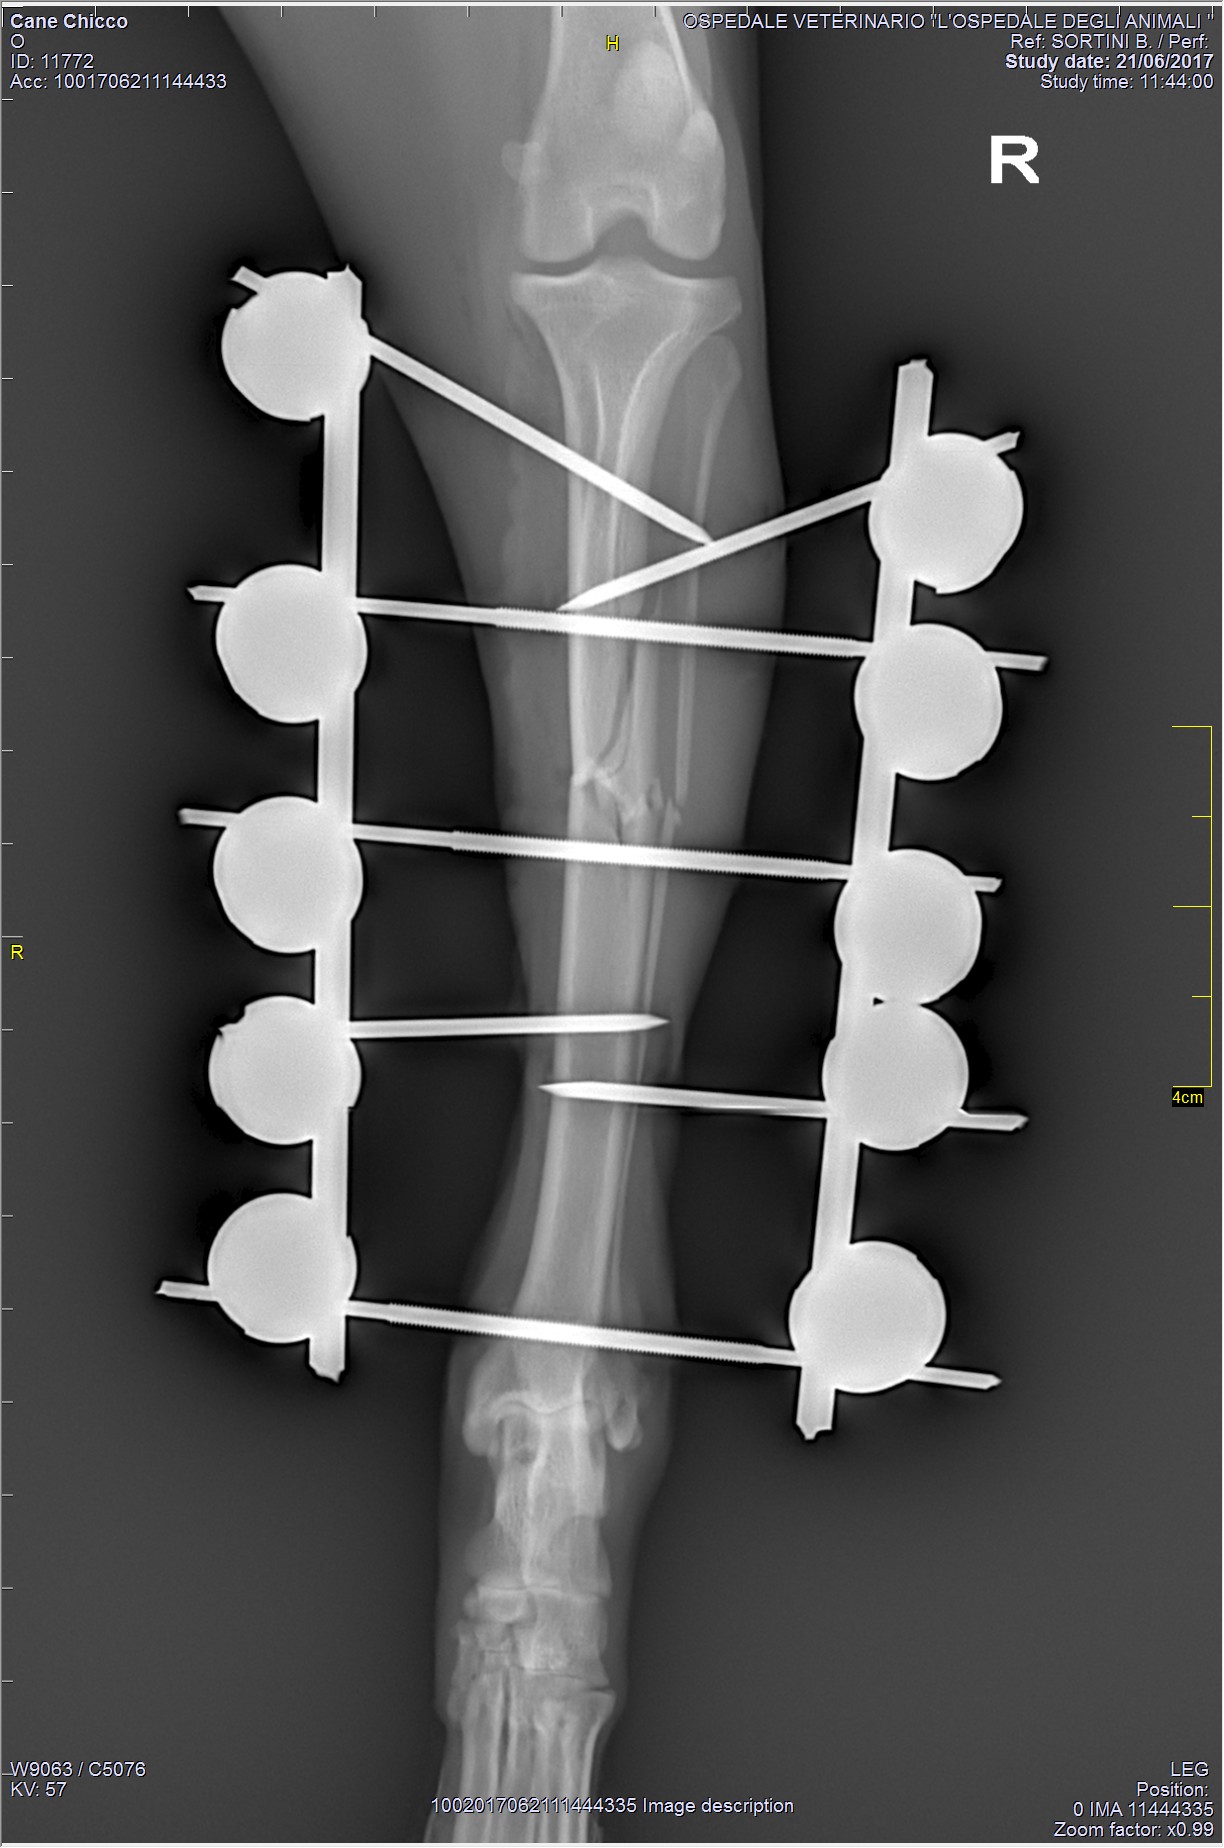

TPLO - Tibial Plateau Leveling Osteotomy

La tecnica TPLO (Osteotomia di livellamento del piatto tibiale) è attualmente una delle metodiche chirurgiche più utilizzate per il trattamento della rottura del legamento crociato craniale nel cane. Essa revede l’esecuzione di un'osteotomia radiale, eseguita con strumentario apposito, la rotazione caudale del segmento prossimale tibiale e la stabilizzazione dei monconi tibiali mediante placca.

Questa tecnica non prevede alcuna sostituzione del legamento crociato in quanto, mediante una modificazione della geometria articolare, permette di ottenere l'annullamento di forze indesiderate. In particolare, mediante la correzione dell’inclinazione del piatto tibiale, si propone di assicurare la stabilità dinamica cranio-caudale a carico dell’articolazione del ginocchio durante la fase d’appoggio del passo.

I vantaggi di questa tecnica chirurgica comprendono la precisione geometrica e il mantenimento nella posizione dell'articolazione del ginocchio, senza modificarne la biomeccanica.